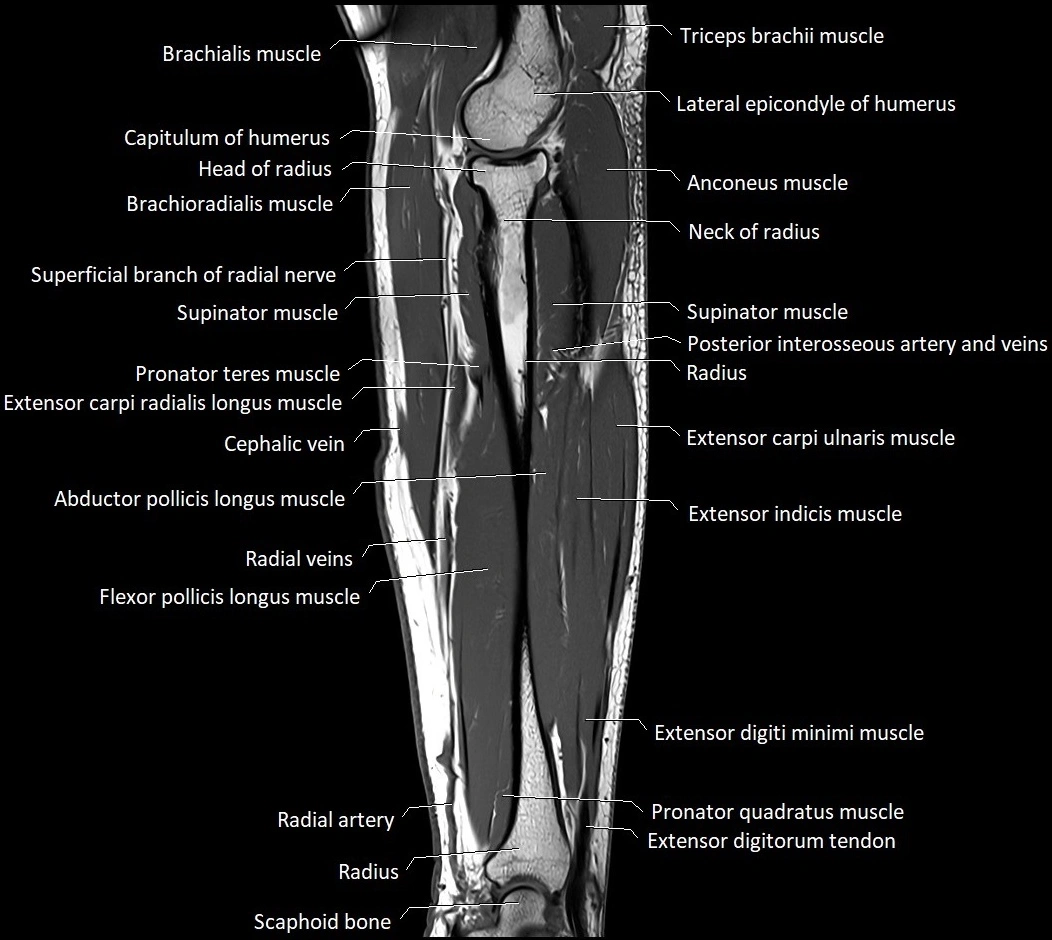

MRI images

image